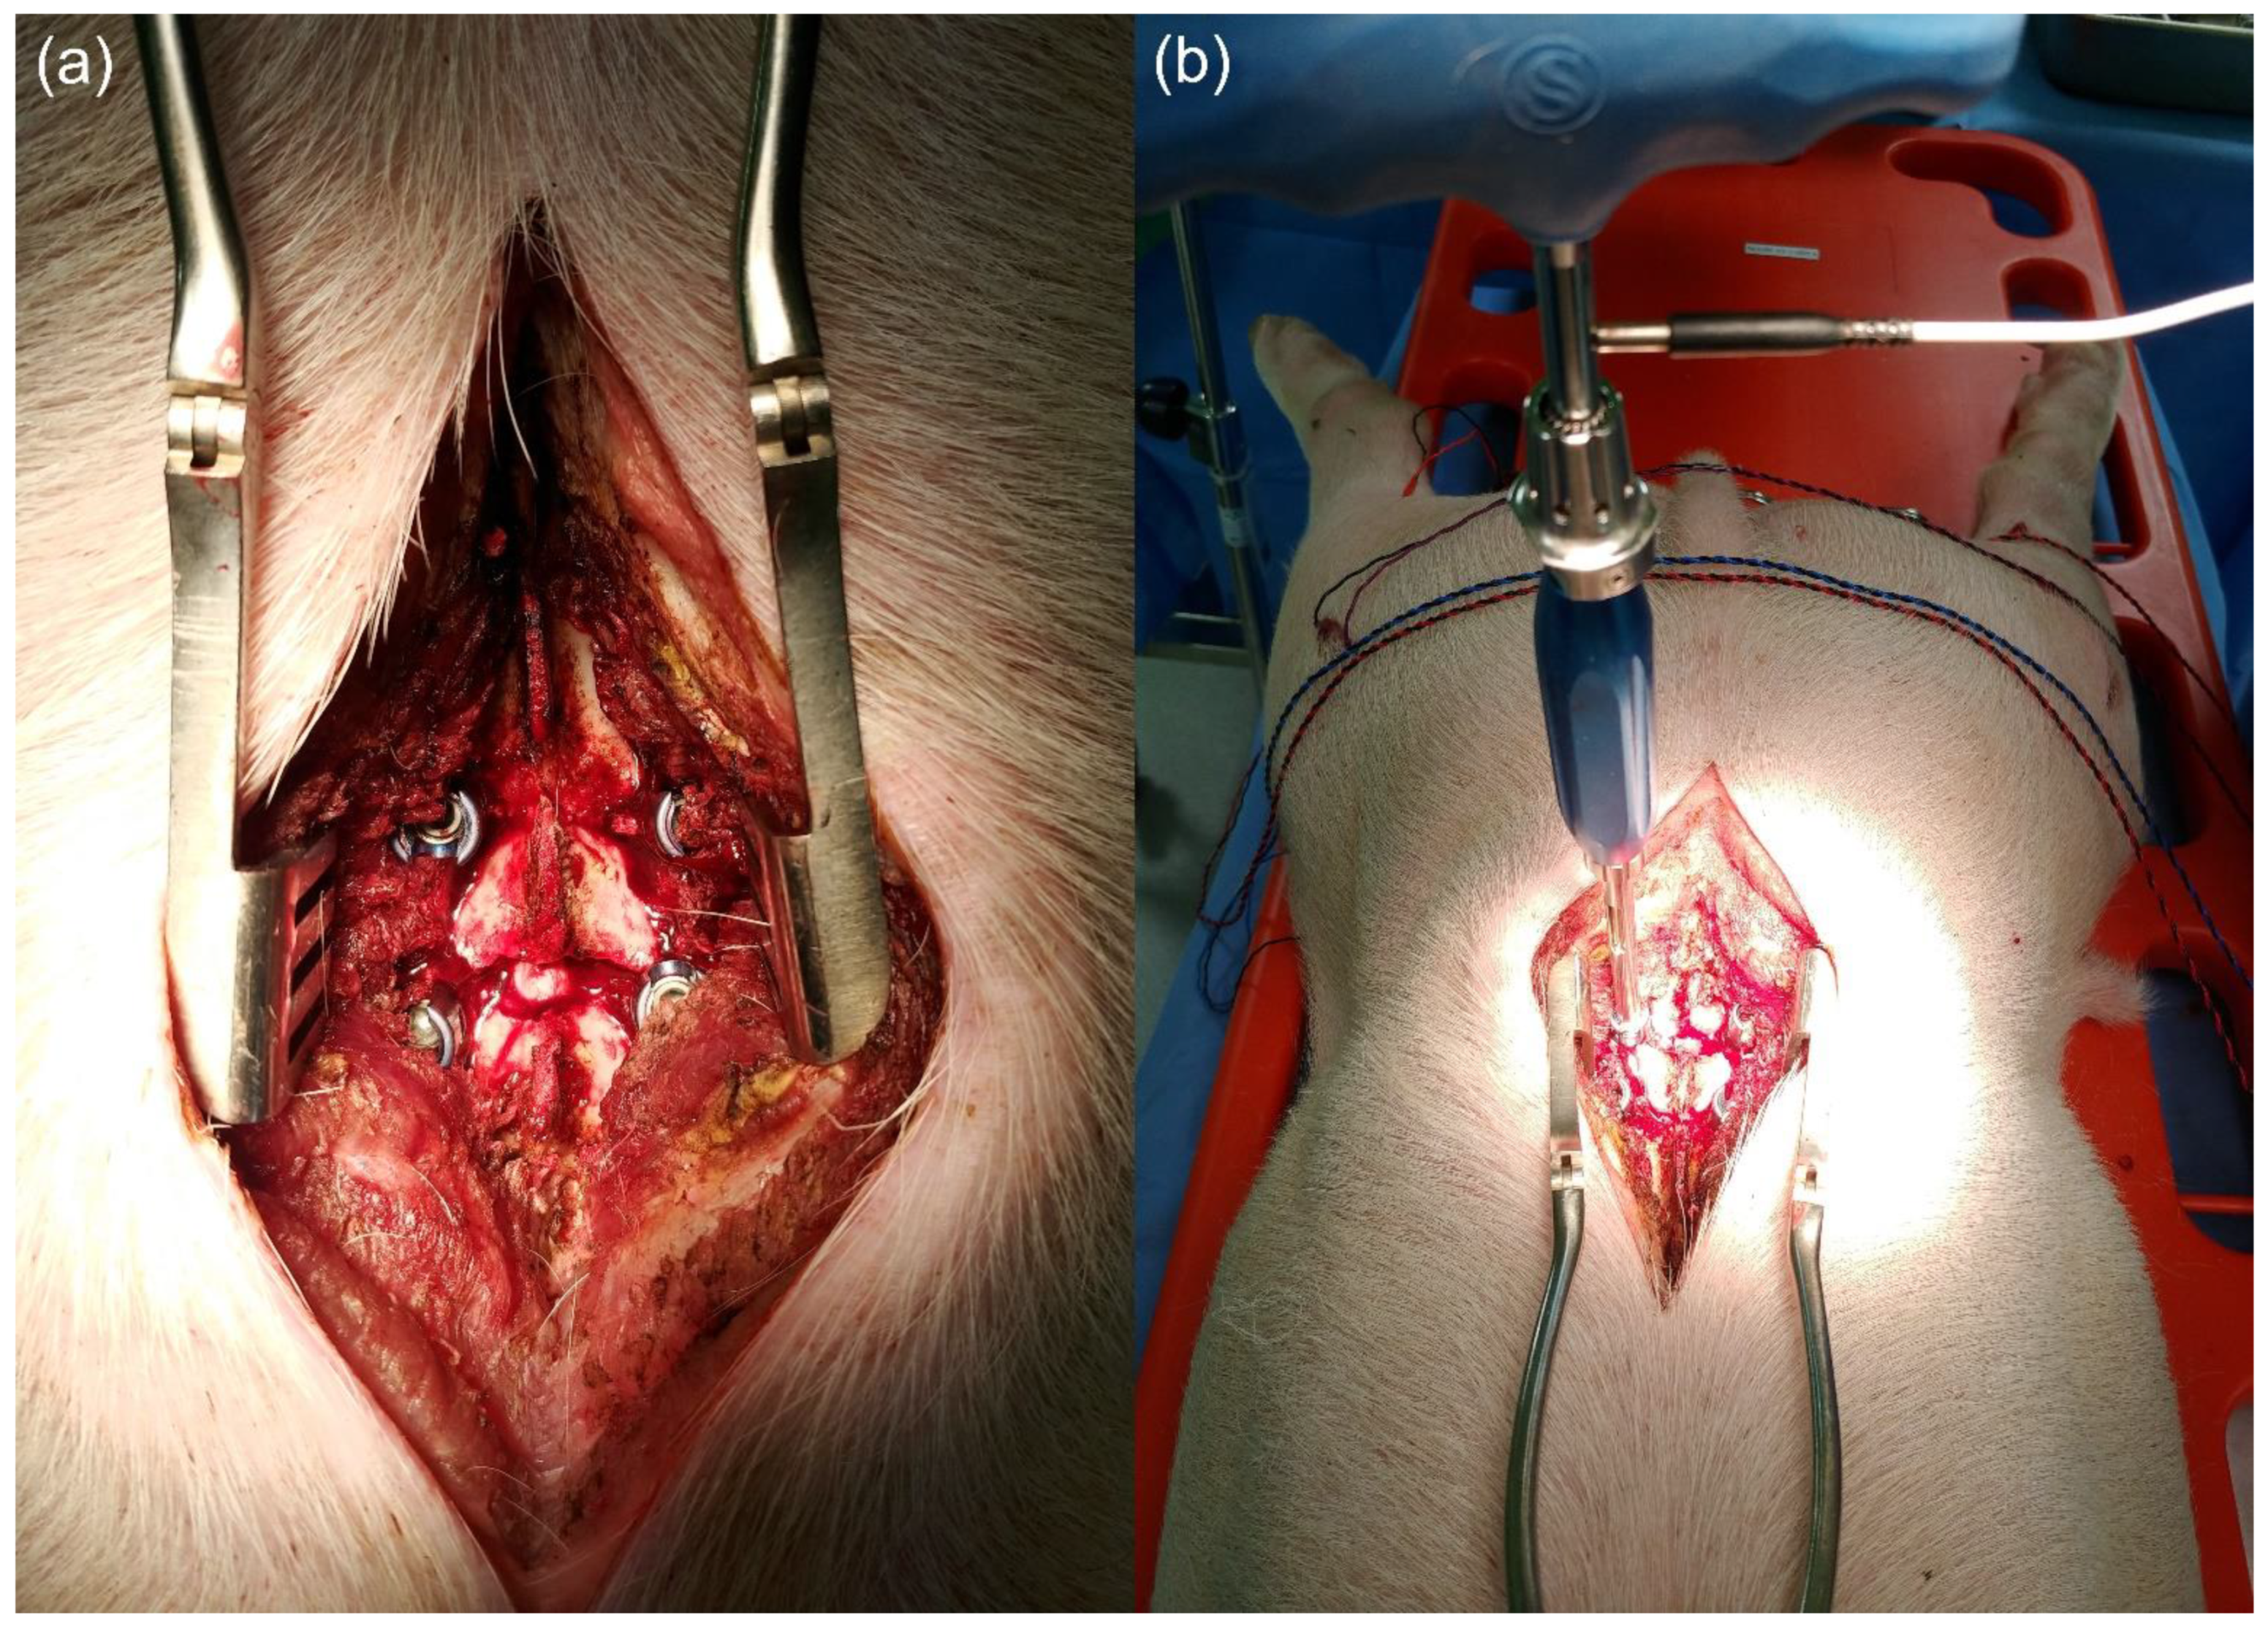

2. Materials and Methods

2.1. Animal Experiment